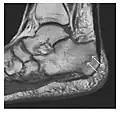

Fatigue fractures are more frequent in women which may be due to the relatively smaller bones of women. Moreover, pregnancy is a well-recognized risk factor for femoral neck fatigue fracture. While fibular and metatarsal fractures have a low risk of complications, other sites including the femoral neck, midanterior tibia, navicular, talar, and other intraarticular fractures are prone to complications such as delayed union, nonunion, and displacement. The site of the insufficiency fracture may be specific to the activity: for example, rugby and basketball players are more prone to navicular fractures, while gymnasts have a higher risk for talar fractures (Figure 7). Long distance runners are at increased risk for pelvic, tibial (Figures 8 and 9), and fibular fractures. In the military, calcaneus (Figure 10) and metatarsals are the most commonly cited injuries, especially in new recruits. Billiard players are at risk for upper limb fractures (Figure 11).[1]

-

a -

b

Figure 7: Fatigue fracture of the talus in a 25-year-old male basketball player with right hind foot and ankle pain, without history of trauma, and a normal initial radiograph (not shown). (a) One-month followup lateral radiograph shows normal appearance. (b) Sagittal T1-weighted MRI shows an irregular fracture line (arrow) within an ill-defined area of hypointensity corresponding to bone marrow edema.[1]